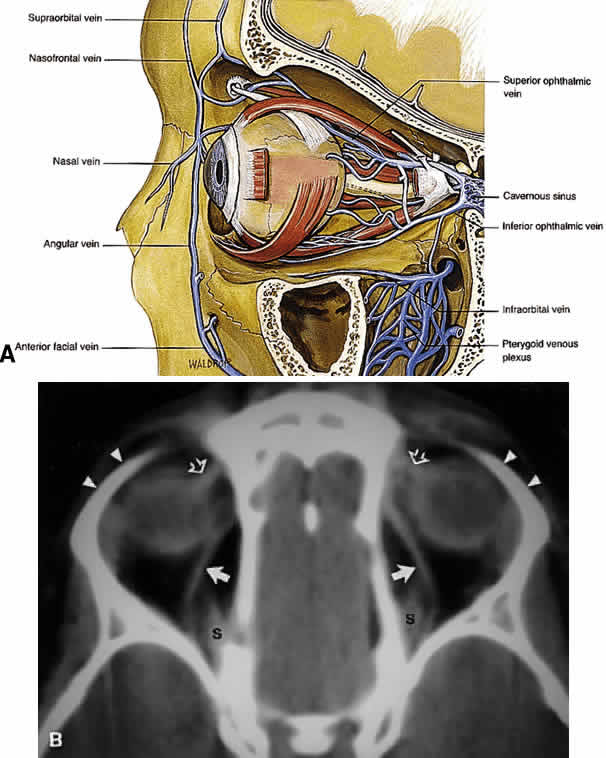

Before giving off the ophthalmic artery, the ICA has several minor branches that supply the meninges, including the dura of the lateral wall of the CS. An abnormal communication between the arterial and venous supply of the CS results in either a carotid-cavernous fistula or a dural-sinus fistula (Fig. 18A). Because of the larger caliber of the ICA, a carotid-cavernous fistula is usually symptomatic secondary to a high flow state, possibly manifesting as orbital/ocular ischemia and increased intraocular pressure. This type of fistula is most commonly encountered in younger patients after blunt trauma and may require invasive neuroradiologic treatment (Fig. 18B). Conversely, a dural-sinus fistula is typically a low-flow state because the abnormal communication forms between the small-caliber dural arterial feeders of the lateral CS wall and the venous plexus of the CS. Such fistulas are usually seen in older individuals as a spontaneous event. Depending on the severity of symptoms, most dural sinus fistulas are simply followed by observation because of the high rate of spontaneous closure.

Fig. 18. Carotid-cavernous fistula. A. Clinical photograph demonstrating tortuosity of the arteriolized episcleral veins, extending up to the limbus (the vascular congestion of conjunctivitis usually ends 1 mm short of the limbus). B. Axial CT shows the difference in caliber between the uninvolved superior ophthalmic vein and the involved vein (arrows). C. Coronal image likewise shows the difference in venous size (arrows). Also note the enlargement of the extraocular muscle on the involved side, indicative of orbital congestion. The superior ophthalmic vein is always found beneath the superior rectus muscle, to which it is tethered by a hammock-like fascial slip. On the involved side, orbital congestion and enlargement of the vein cause distortion of this anatomic relation. D. Parasagittal arteriography image of a different patient shows abnormal arterial filling of the CS, extending anteriorly into the orbit through an engorged superior ophthalmic vein (SOV).

The major venous drainage of the orbit is the superior ophthalmic vein and the CS (Fig. 21). The superior ophthalmic vein follows a medial-to-lateral route posteriorly along the superior orbit, tethered beneath the superior rectus muscle by a fascial sling.19 At the orbital apex, it is usually joined by the inferior ophthalmic vein, which also communicates through more minor branches with the pterygopalatine plexus through the IOF. The central retinal vein typically drains directly into the CS without joining the superior ophthalmic vein. Anteriorly, the orbit also drains into the angular vein of the facial plexus.

Fig. 21. A. Venous drainage of the orbit. Major drainage is supplied by the superior ophthalmic vein, which drains into the CS. Note that the central retinal vein usually drains directly into the CS. Drainage through the pterygoid plexus is minor under normal conditions but becomes very important during outflow problems through the CS (carotid-cavernous or dural-cavernous fistulas). B. Axial CT reveals the course of the superior ophthalmic veins (closed arrows) beneath the superior rectus muscles (S). Also imaged are the superior orbital rims (arrowheads) and the superior oblique muscles (open arrows) as each passes through the trochlea. (A from Dutton JJ: Atlas of Clinical and Surgical Orbital Anatomy, p 79. Philadelphia, WB Saunders, 1994)